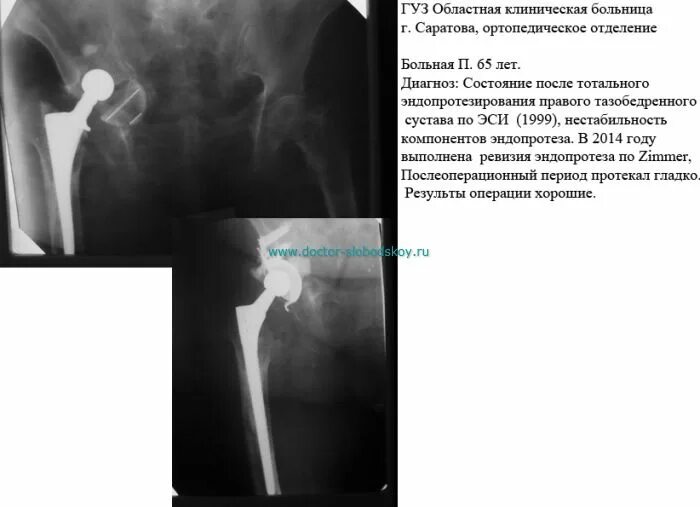

Нестабильность тазобедренного сустава